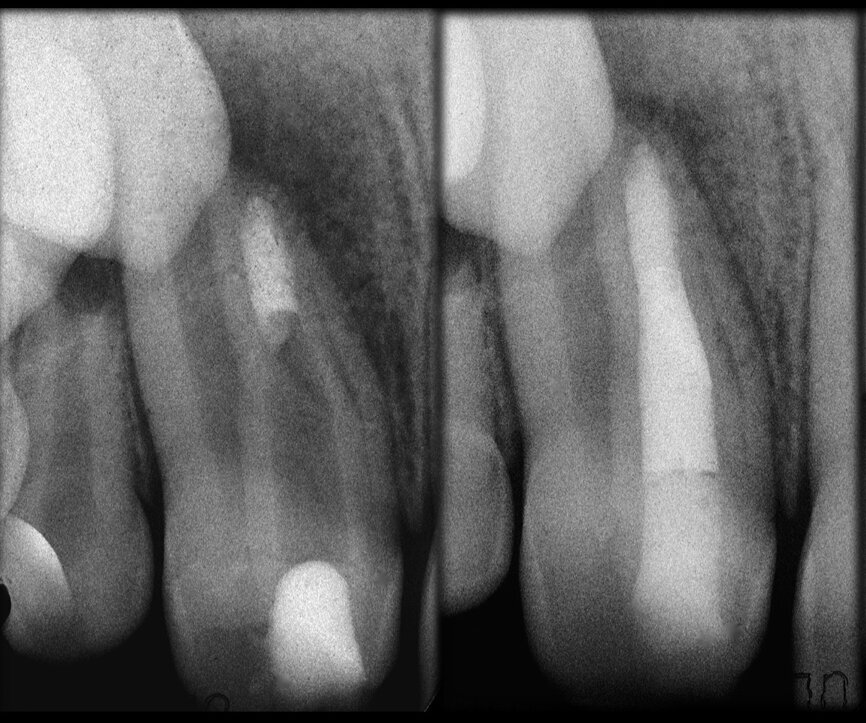

In the maxillary premolar shown in Figures 5 and 6, the fistulogram revealed the presence of an apical lesion that extended coronally to approximately the middle third of the root. The clinical decision could, therefore, propend towards orthograde retreatment; however, CBCT gave us a very different view of the situation compared with the radiograph, as it indicated that a prior treatment had irreversibly damaged the tooth, which would therefore have to be extracted.